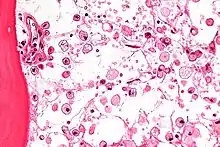

The disease is caused by a defect in the housekeeping gene for lysosomal glucocerebrosidase (also known as beta-glucosidase, EC 3.2.1.45, PDB: 1OGS) on the first chromosome (1q22). The enzyme is a 55.6-kilodalton, 497-amino acid-long protein that catalyses the breakdown of glucocerebroside, a cell membrane constituent of red and white blood cells. In Gaucher disease, the enzyme is unable to function correctly and glucocerebroside accumulates. The macrophages that clear these cells are unable to eliminate the waste product, which accumulates in fibrils, and turn into 'Gaucher cells', which appear on light microscopy to resemble crumpled-up paper.[3]

A diagnosis can also be implied by biochemical abnormalities such as high alkaline phosphatase, angiotensin-converting enzyme, and immunoglobulin levels, or by cell analysis showing "crinkled paper" cytoplasm and glycolipid-laden macrophages.